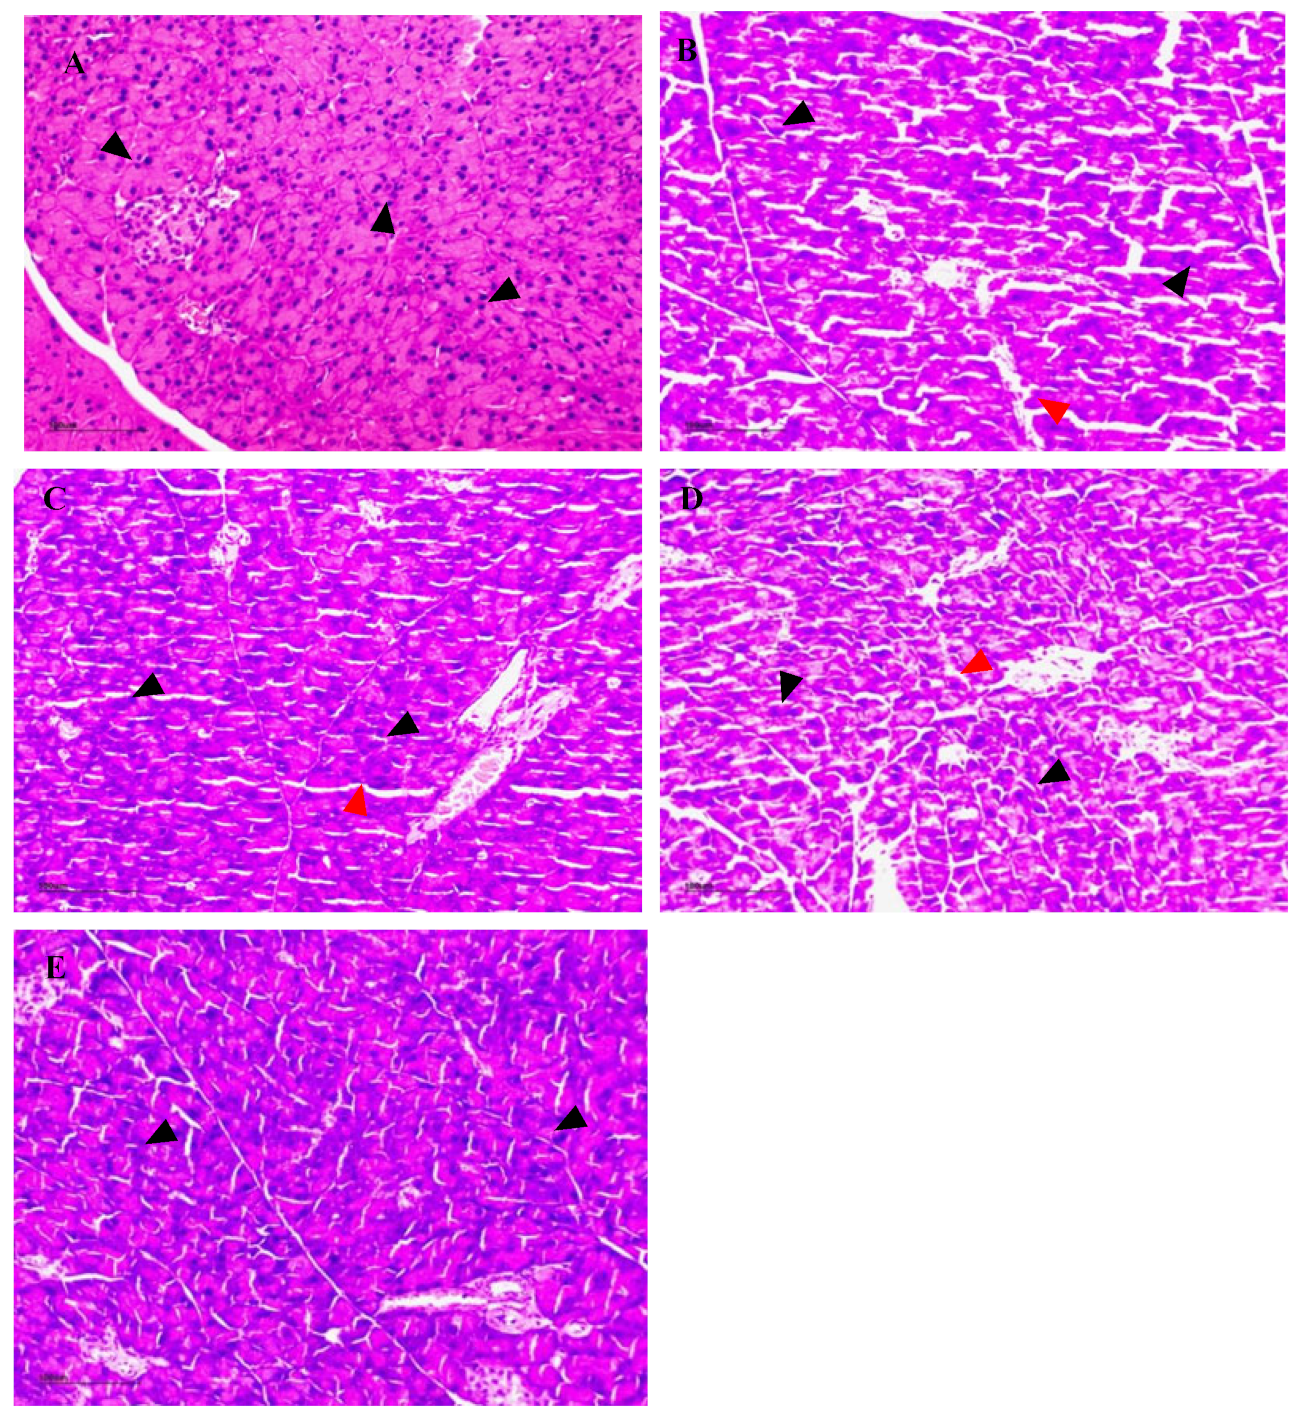

3.16. The Effect of NSPs on Pancreas Histology